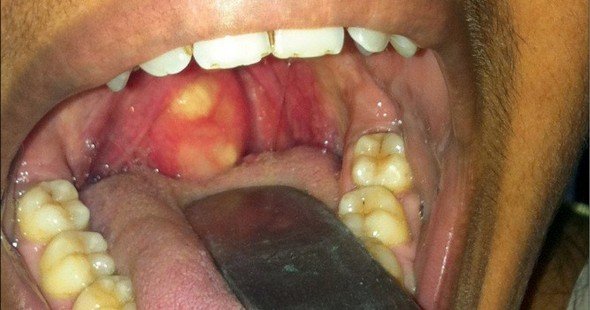

При подозрении на наличие заглоточного абсцесса врач проводит фарингоскопию, то есть осмотр задней стенки глотки с использованием специального небольшого зеркала. В результате осмотра может быть обнаружена опухоль с наличием жидкого содержимого, что проявляется колебанием стенок. В начальной стадии шарообразное выпячивание находится с одной стороны, а затем перемещается в центр глотки. Если возникают сомнения относительно диагноза, через стенку абсцесса вводят шприц для извлечения гнойного содержимого.

- осмотр горла (фарингоскопия) – позволяет выявить покраснение и отек слизистой оболочки, покрывающей заднюю стенку глотки;